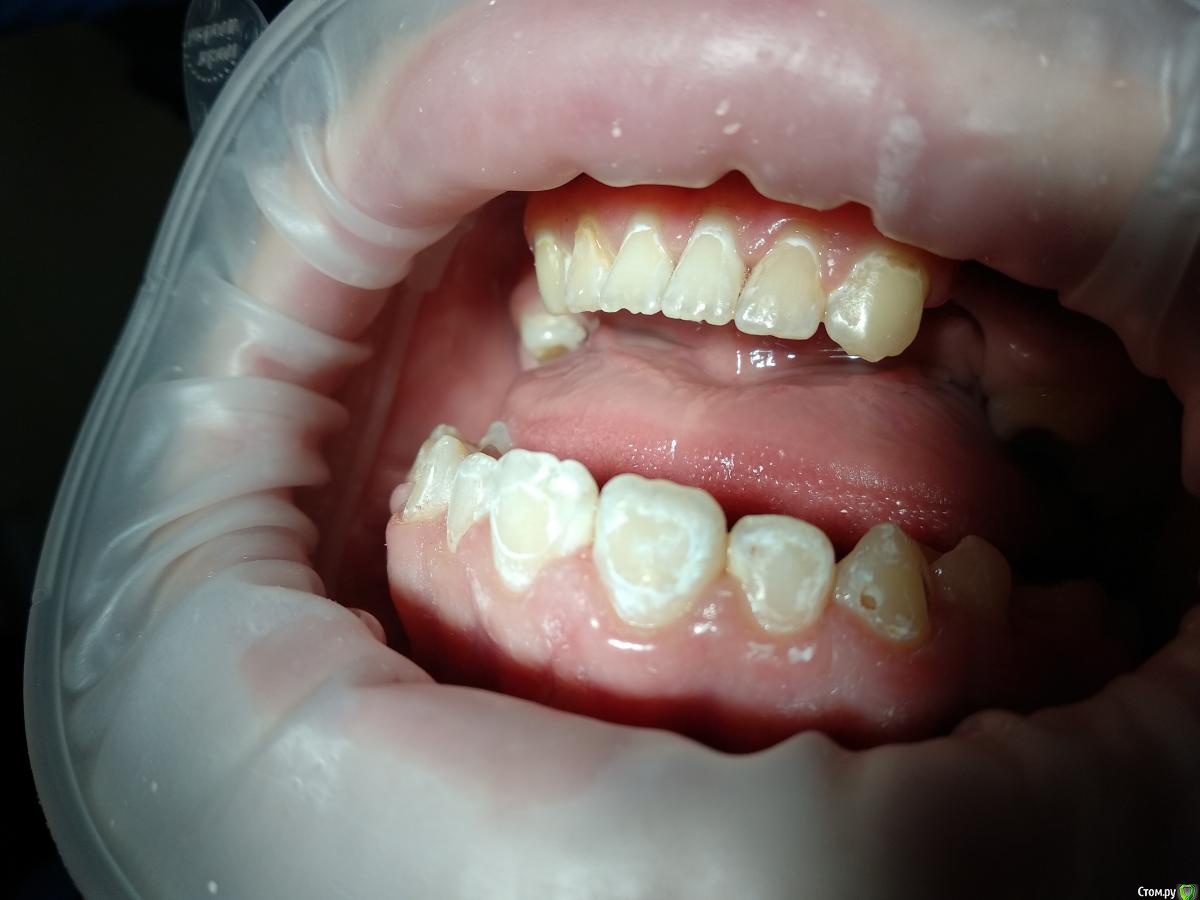

Paganini Опубликовано 13 октября, 2018 Поделиться Опубликовано 13 октября, 2018 (изменено) Приветствую! Помогите помочь пациенту (13 лет). Попросила ортодонта снять брекеты досрочно, потому что с эмалью беда - эмаль скалывается кусками, в местах под брекетами множественные дефекты. При нажатии на эмаль зондом остаются следы. Уверена, что до установки брекетов была уже патология (флюороз или гипоплазия), брекеты всего лишь усугубили ситуацию. С гигиеной тоже все плохо: всегда, когда пациент приходил ко мне на чистку, налета столько, что хоть ложкой снимай... Ставить пломбы? Дефектов очень много, и я думаю, что держаться это будет плохо, эмаль хрупкая. Сейчас комплексно укрепляем эмаль.P.S.: я не детский врач. Я гигиенист и терапевт с небольшим опытом работы. Изменено 13 октября, 2018 пользователем Paganini Ссылка на комментарий

Paganini Опубликовано 13 октября, 2018 Автор Поделиться Опубликовано 13 октября, 2018 Пострадали почти все резцы и клыки, жевательная группа в порядке, но там мало что есть (первичная адентия). Ссылка на комментарий

St. Опубликовано 14 октября, 2018 Поделиться Опубликовано 14 октября, 2018 1. учить чистить, мотивировать и контролировать домашнюю гигиену, без этого толку не будет. если необходимо чаще вызывать на проф.гигиену2. пломбировка где уже есть дефекты эмали.3. рем терапия или возможно айкон где только пятна без дефекта. 1 Ссылка на комментарий